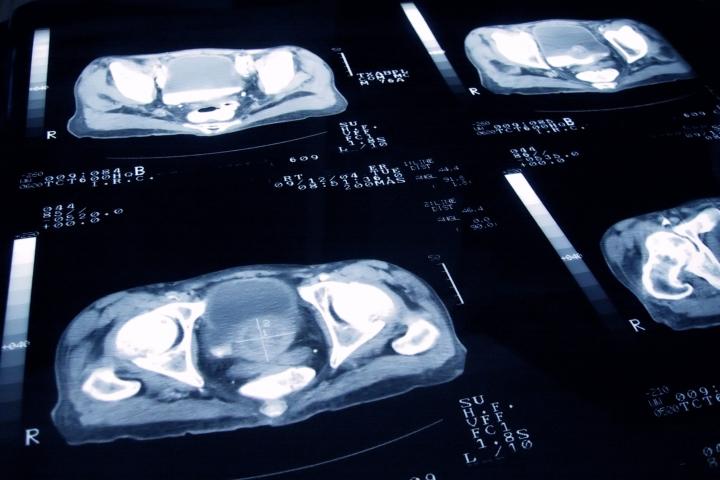

El cáncer de próstata es una de las principales causas de muerte en todo el mundo, según la Organización Mundial de la Salud (OMS). Sólo en 2020, se detectaron un total de 1,41 millones de casos, en datos del ya citado organismo. En este contexto, hay una búsqueda de innovación tecnológica que ayude a paliar este tipo de enfermedades.

El cáncer de próstata es "el primer tumor más frecuente en hombres", según la Asociación de Cáncer de Próstata en España. Y, aunque los datos apuntan a que 3 de cada 4 pacientes con tumores localizados de estas características se curarán, la asociación subraya la importancia de detectarlo rápidamente.